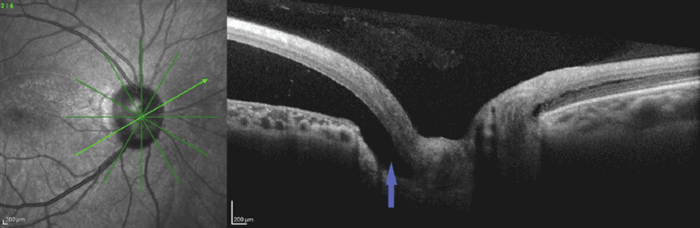

При исследовании области ДЗН с темпоральной стороны обнаружена связь ОНЭ со структурами ДЗН, в той же зоне наблюдалась инвагинация слоя нервных волокон сетчатки (СНВС) в структуры ДЗН, что позволило подтвердить диагноз ямки ДЗН (рис. 6).

Рис. 6. ОКТ пациентки Б. Радиальный срез через центр экскавации диска зрительного нерва (стрелка — связь отслойки нейроэпителия со структурами диска зрительного нерва)

Fig. 6. OCT of patient B. Radial scan across the optic disc cup center (arrow – connection of neuroepithelium detachment with optic disc structures)

ОКТ-признаками ямки ДЗН являются связь структур ДЗН с субретинальным пространством, а также инвагинация слоя нервных волокон сетчатки в структуры ДЗН.